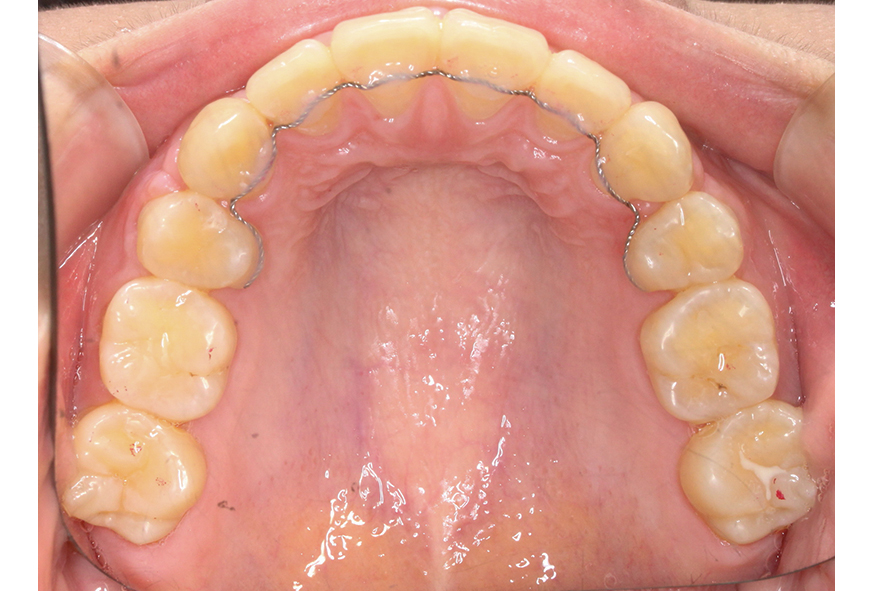

상악 교합면을 보면 전치부 치아의 각도가

순측으로 뻐드러지듯 누워있는 모습과 함께

억궁의 길이가 긴 장안모 경향을 보이는 모습인데요,

이러한 경우 하악과의 교합을 맞추기 위해

상악 치아를 발치한 후 공간을 닫아

악궁의 길이를 줄일 수 있습니다.

상악의 교합면을 보시면 교정 전 모습과 달리

악궁의 길이가 짧아지고 안모의 길이도

줄어든 모습으로 소구치 발치 후 공간을

닫는 것에 영향을 받은 것으로 보입니다.